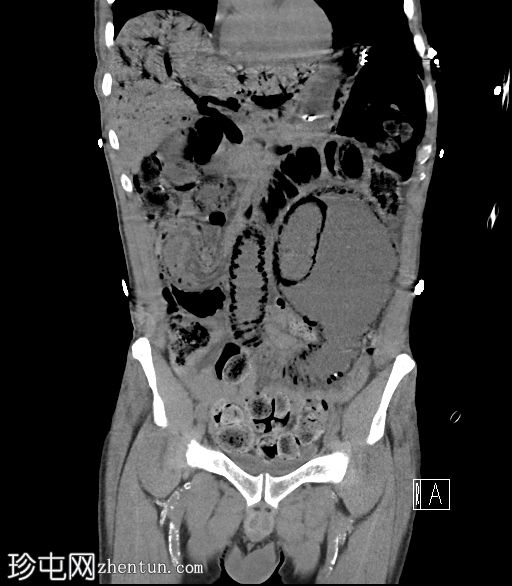

CT

冠状位片

平扫

门静脉积气。胃管末端位于胃底。下腹部可见长段小肠套叠,套叠起始点位于右下腹。伴有远端小肠广泛积气,左下腹肠段扩张,最符合小肠梗阻和缺血的表现,可能由长段小肠套叠引起。

病例讨论

门静脉积气通常预后不良,但该患者最终存活并出院。当肝脏内出现气体时,鉴别诊断包括胆道积气(胆道积气)和门静脉积气。通常区分并不困难:胆道积气聚集在肝脏中央,方向与胆汁流动方向一致;而门静脉积气则位于肝脏外周,方向与门静脉血流方向一致(由中央向外周)。